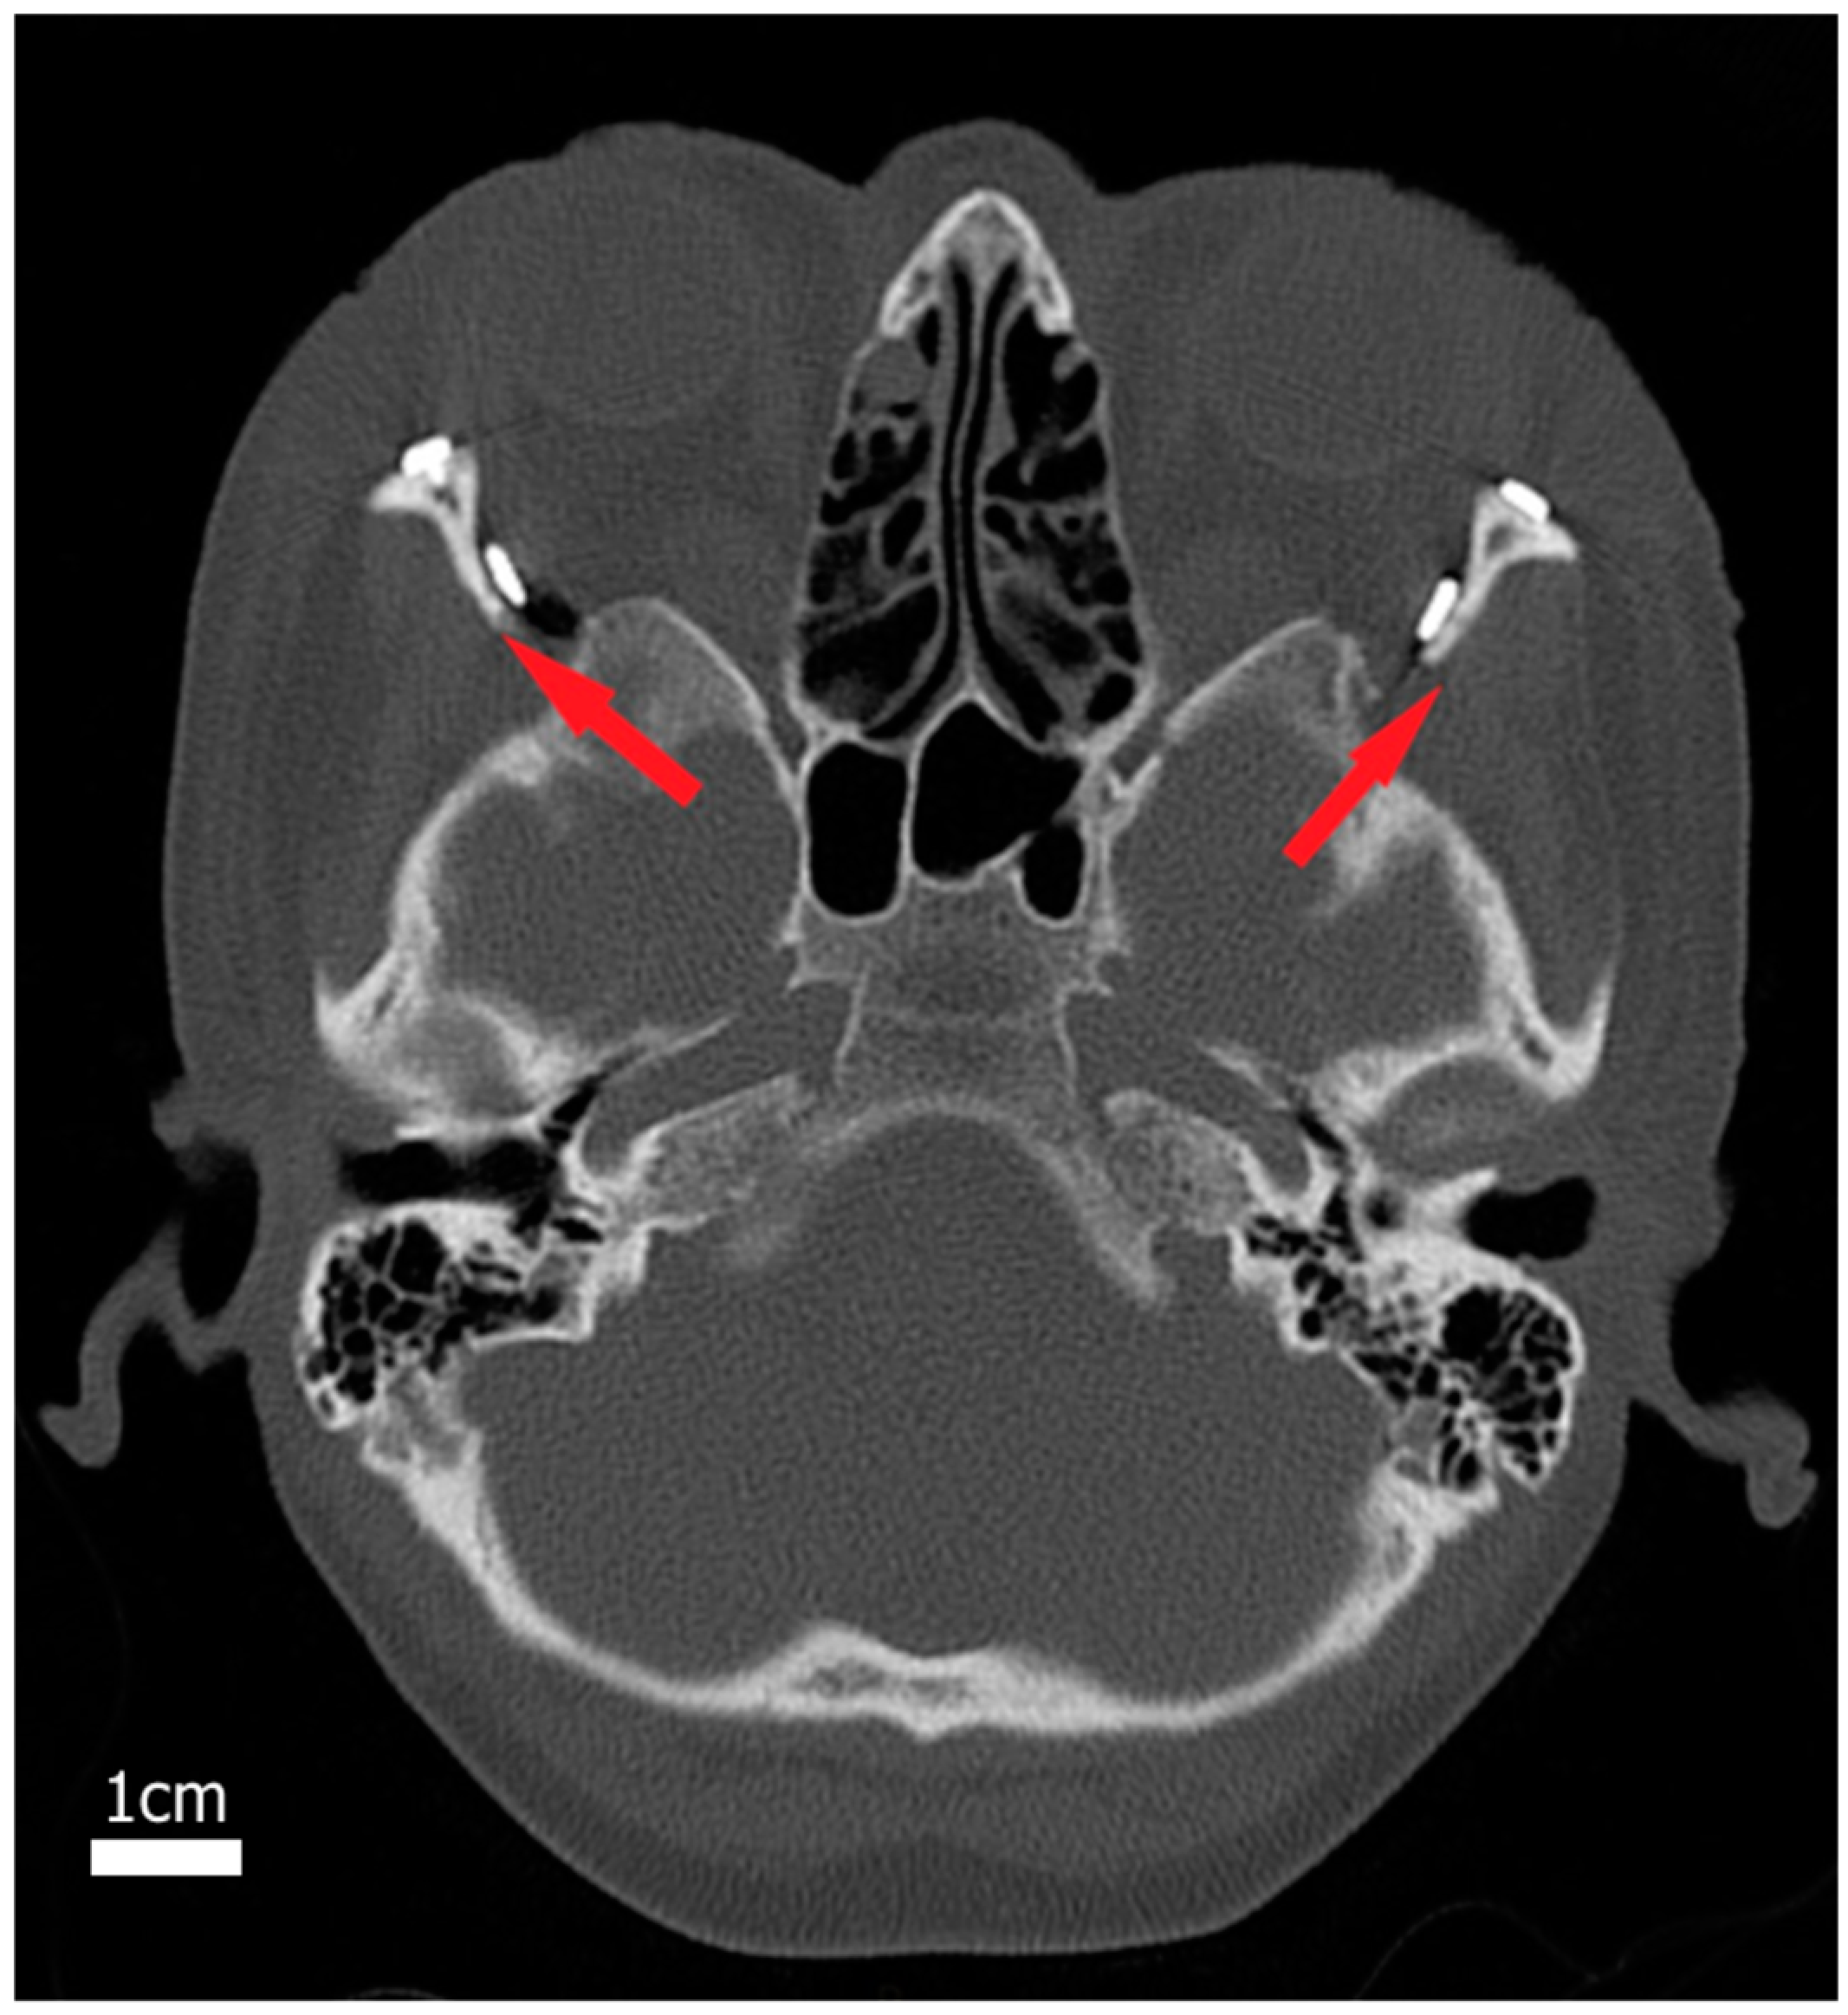

2.1. Surgical Procedure

2.2. Study Design

2.3. Three-Dimensional Image Processing and Orbital Model Generation

2.4. Physics-Based Simulation of Decompression Surgery